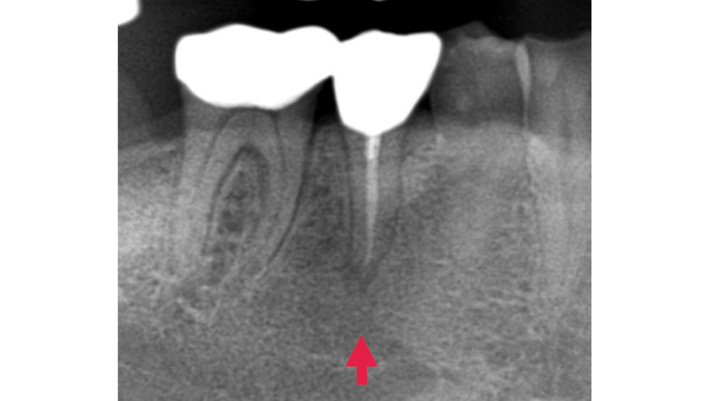

治療前

治療後

治療の経緯

患者様は「何度も腫れる」「根の治療を繰り返している」とのお悩みで来院されました。診査の結果、歯の根の先に膿の袋(根尖病変)が確認され、過去の治療で細菌が十分に取り除けていない可能性が考えられました。そこで、ラバーダムを使用して治療部位への細菌の侵入を防ぎながら、拡大視野下で精密な根管治療の再治療を行い、感染源の徹底的な除去を行いました。

| 主訴 | 右下が腫れて痛い |

|---|---|

| 治療期間 | 1ヶ月 |

| 治療費 | 保険適用 |

| 治療内容 | レントゲンで確認すると、根尖病変が認められ根管治療を行いました。 |

| 治療のリスク | 再発が起きる場合は、外科処置を追加で必要なケースがあります。 |